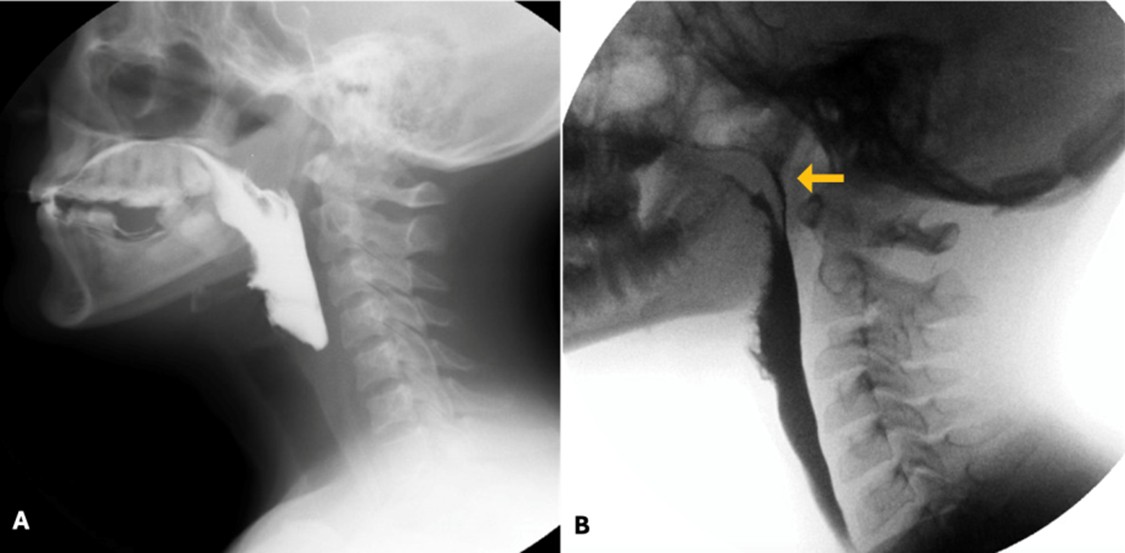

Under normal conditions, during the passage of food through the pharynx, the nasopharynx is closed by the velopharyngeal valve. When this mechanism is defective, food may enter the nasopharynx and/or the nasal cavity, typically due to weakness of the muscles of the soft palate. (Fig. 12)

Figure 12: Normal nasopharyngeal sealing mechanism (A) and penetration of contrast into the nasopharynx (orange arrow in B)